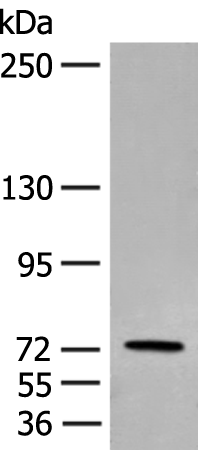

WB Predicted band size: |

78 kDa |

WB Positive control: |

Human bladder transitional cell carcinoma grade 2-3 tissue lysate |

WB Recommended dilution: |

200-1000 |